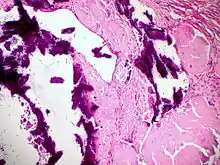

Dystrophische Verkalkung (violett) bei Lymphknotenamyloidose, H&E.